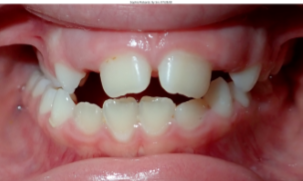

| Posterior Crossbite | The top teeth in the back are inside the bottom teeth in the back. Either on one side or both. | ![]() | In a child, the roof of the mouth is 2 separate bones that can be easity separated to widen the upper jaw. During adolence, the 2 bones fuse in to a single bone, making it more difficult and invasive to widen the jaw. |